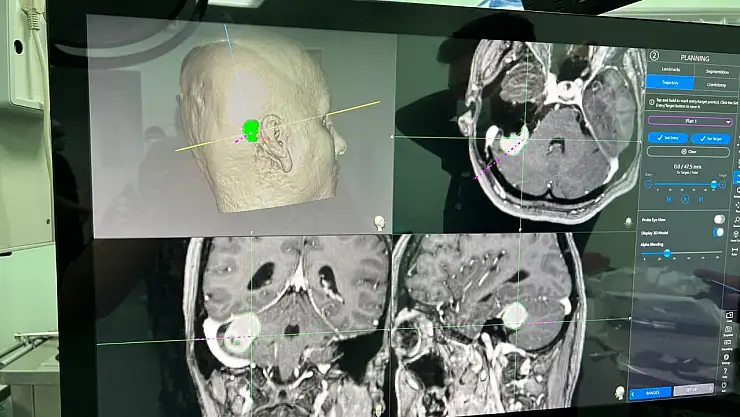

Beyin zarından kaynaklı tümörü olan hastanın 1 gün yoğun bakımda kaldığını, yarın da taburcu edileceğini söyleyen Op. Dr. Burak Yürük, "Bu ameliyatın daha konforlu, güvenli olması için yüze, yanağa ve dile giden sinirleri montize ettik. Görüntülemesini yaptık. Aynı zamanda ince kesik tetkiklerini elde ederek hem ameliyat sırasında, hem ameliyat sonrasında bize yol gösterici navigasyon dediğimiz bir haritalama yaparak tümörün tamamına yakınını boşalttık. Ameliyat sonrası filminde de hasta, mevcut baskı oluşturacak bir kitle lezyonu artık göstermiyor" diye konuştu.